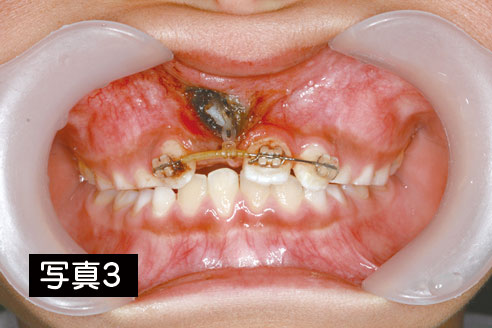

数か月様子をみましたが、この歯が自然に出てくる気配が全くなかったため、開窓・牽引術を施行しました。歯はかなり上方にあることが分かります。【写真3】